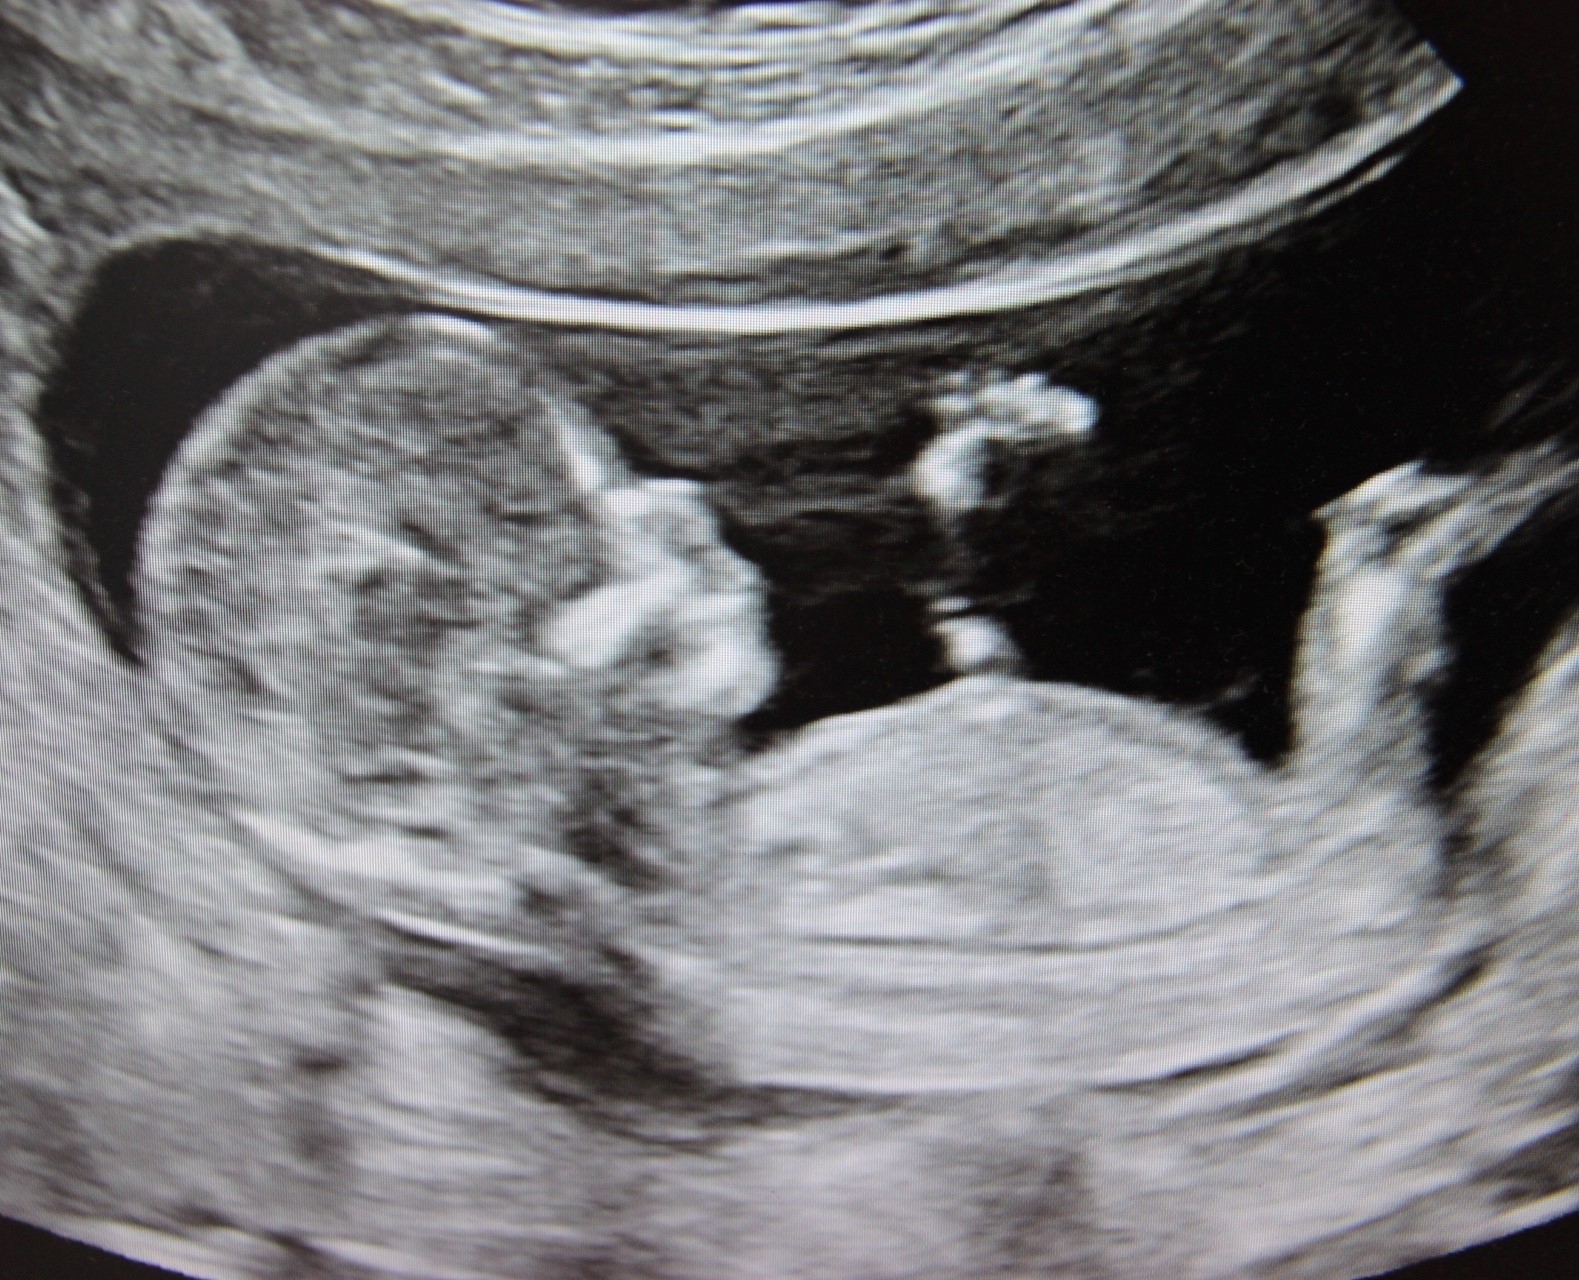

Erste Ultraschalluntersuchung

weitere Ultraschalluntersuchungen auf Wunsch (IGeL)

Ersttrimesterscreening mit Nackentransparenzmessung (IGeL)

Ultraschall zum Ausschluss von Fehlbildungen

Fetale Echokardiographie (Ultraschall des fetalen Herzens)

Dopplersonographie (Untersuchung des Blutflusses in mütterlichen und kindlichen Gefäßen) – bei entsprechender Indikation